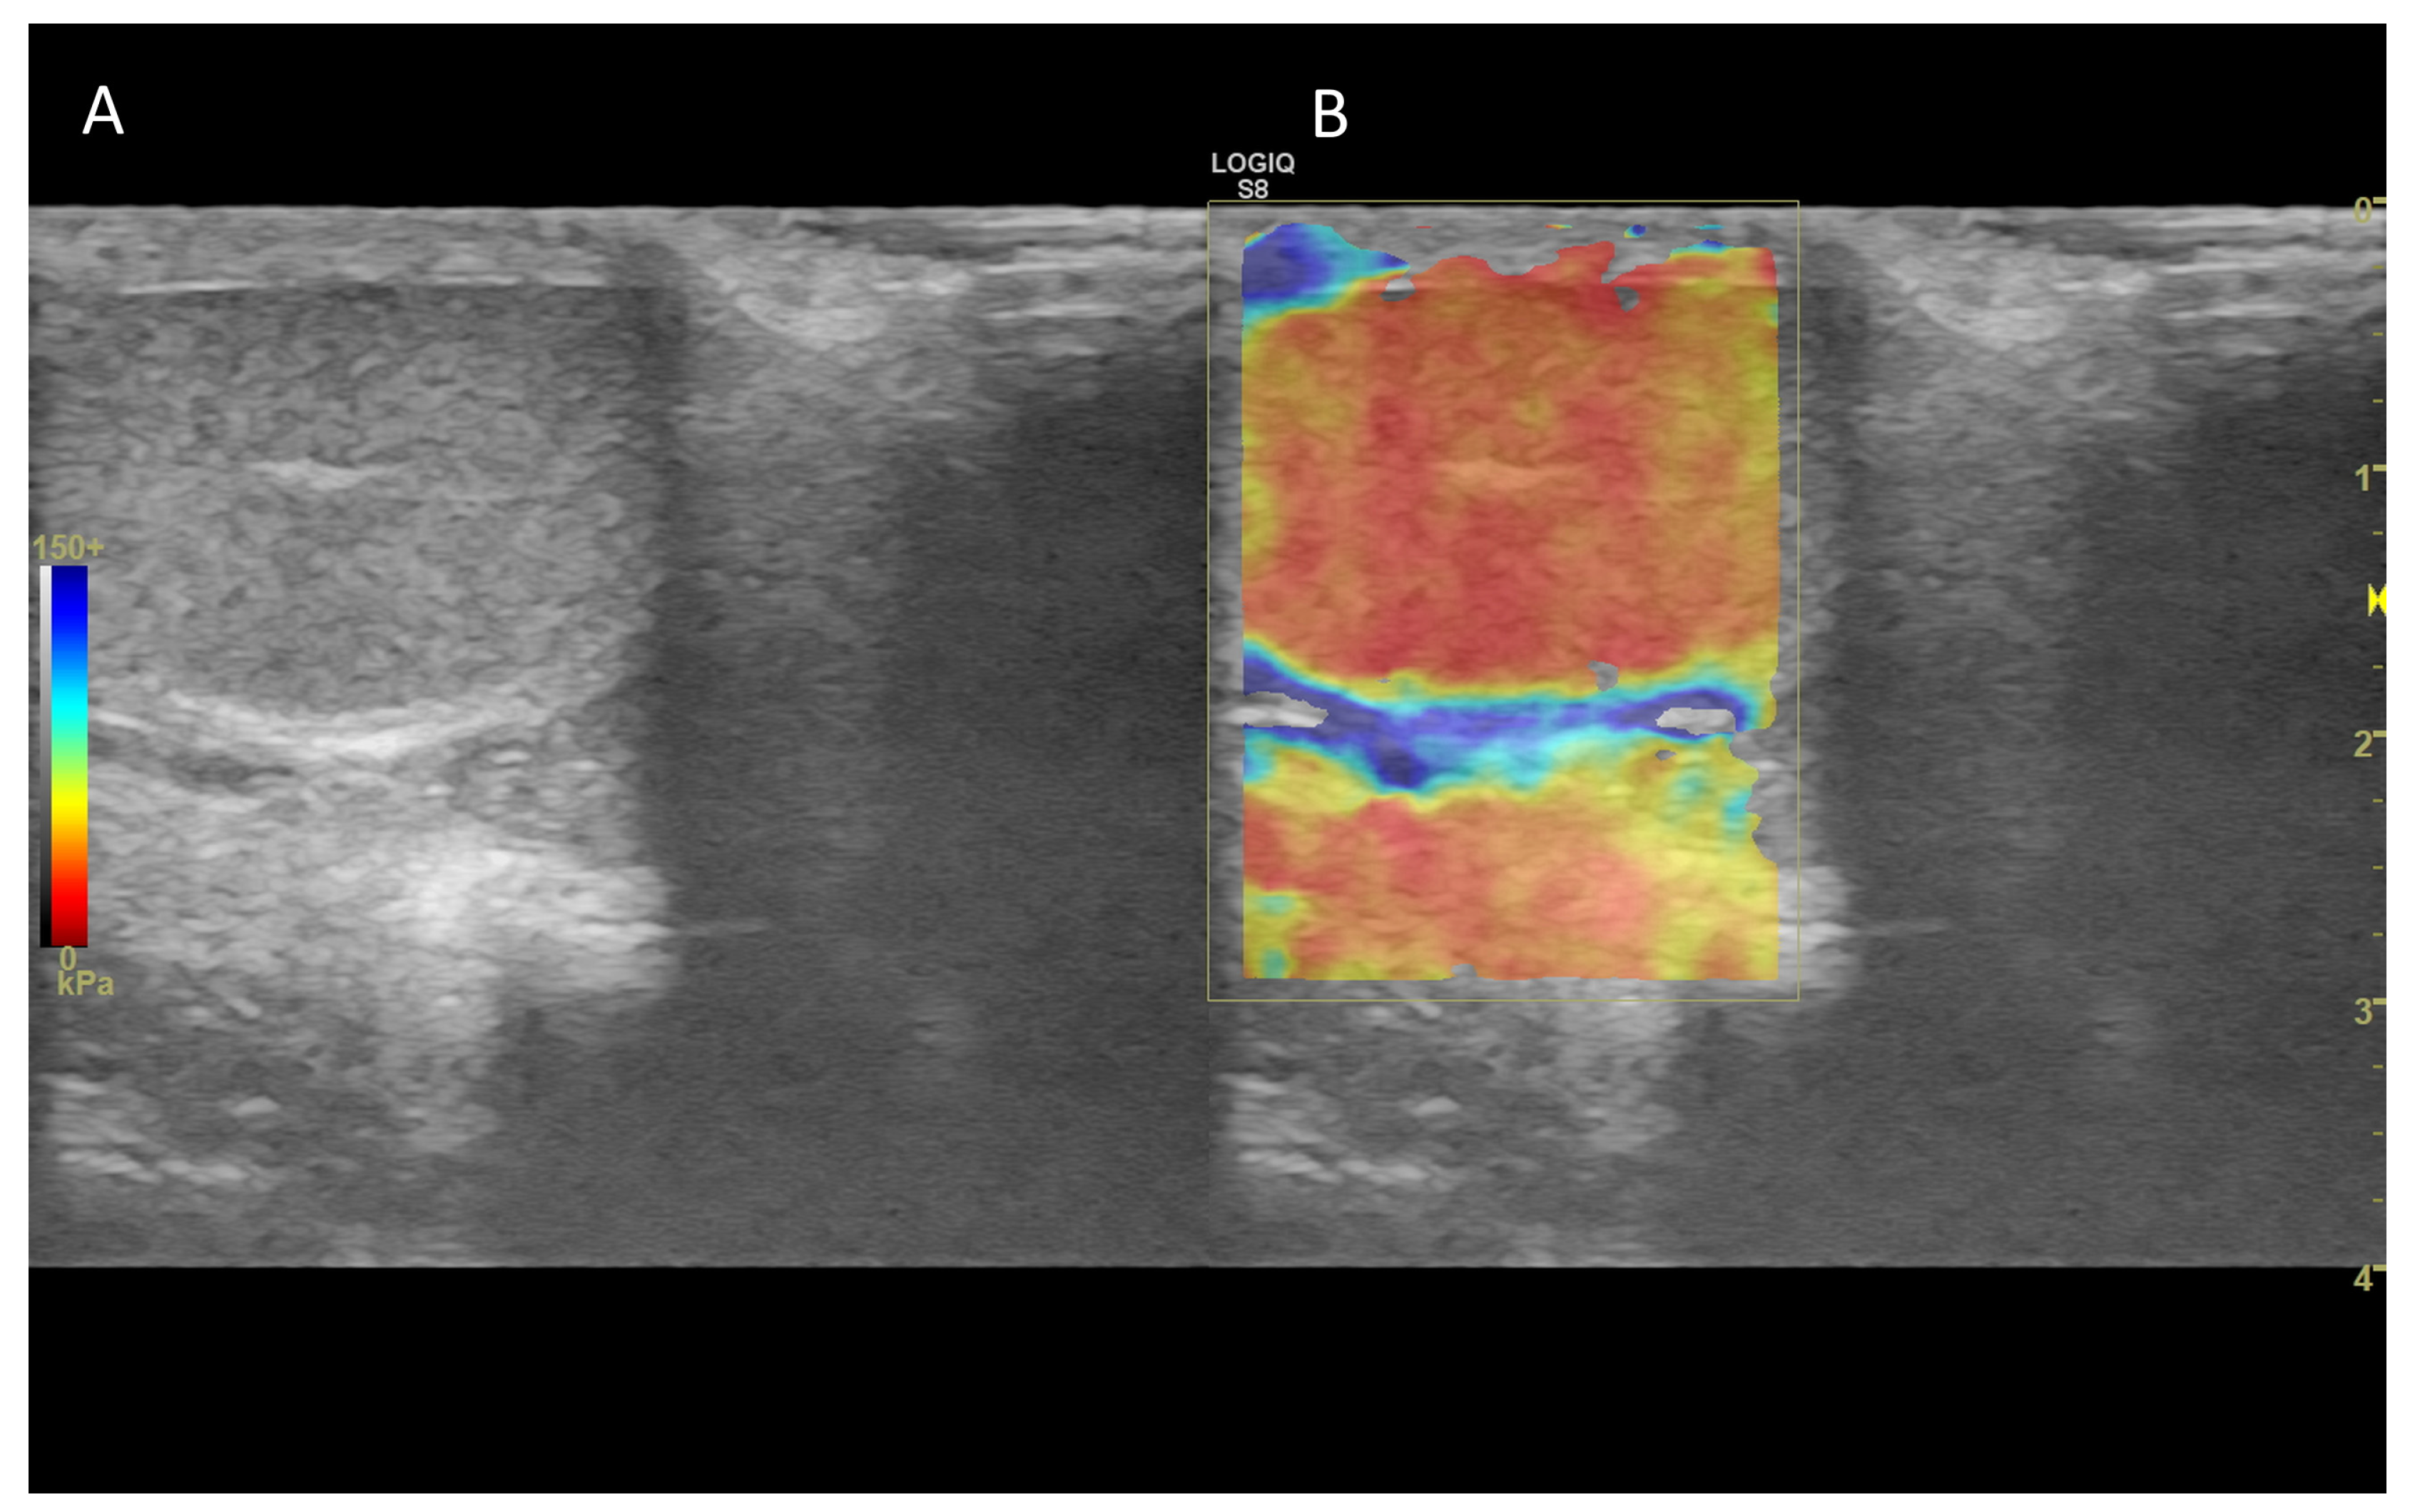

7. Ultrasound Elastography

7.1. Technology and Applications

7.2. Normal Findings

7.3. Abnormal Findings

- Correas, J.M.; Drakonakis, E.; Isidori, A.M.; Hélénon, O.; Pozza, C.; Cantisani, V.; Di Leo, N.; Maghella, F.; Rubini, A.; Drudi, F.M.; et al. Update on Ultrasound Elastography: Miscellanea. Prostate, Testicle, Musculo-Skeletal. Eur. J. Radiol. 2013, 82, 1904–1912. [Google Scholar] [CrossRef]

- Bamber, J.; Cosgrove, D.; Dietrich, C.; Fromageau, J.; Bojunga, J.; Calliada, F.; Cantisani, V.; Correas, J.-M.; D’Onofrio, M.; Drakonaki, E.; et al. EFSUMB Guidelines and Recommendations on the Clinical Use of Ultrasound Elastography. Part 1: Basic Principles and Technology. Ultraschall Med. 2013, 34, 169–184. [Google Scholar] [CrossRef]

- Sigrist, R.M.S.; Liau, J.; Kaffas, A.E.; Chammas, M.C.; Willmann, J.K. Ultrasound Elastography: Review of Techniques and Clinical Applications. Theranostics 2017, 7, 1303–1329. [Google Scholar] [CrossRef]

- Goddi, A.; Sacchi, A.; Magistretti, G.; Almolla, J.; Salvadore, M. Real-Time Tissue Elastography for Testicular Lesion Assessment. Eur. Radiol. 2012, 22, 721–730. [Google Scholar] [CrossRef] [PubMed]

- Muršić, M. The Role of Ultrasound Elastography in the Diagnosis of Pathologic Conditions of Testicles and Scrotum. Acta Clin. Croat. 2021, 60, 41–49. [Google Scholar] [CrossRef] [PubMed]

- Rocher, L.; Criton, A.; Gennisson, J.-L.; Izard, V.; Ferlicot, S.; Tanter, M.; Benoit, G.; Bellin, M.F.; Correas, J.-M. Testicular Shear Wave Elastography in Normal and Infertile Men: A Prospective Study on 601 Patients. Ultrasound Med. Biol. 2017, 43, 782–789. [Google Scholar] [CrossRef]

- Feliciano, M.A.R.; Maronezi, M.C.; Simões, A.P.R.; Maciel, G.S.; Pavan, L.; Gasser, B.; Silva, P.; Uscategui, R.R.; Carvalho, C.F.; Canola, J.C.; et al. Acoustic Radiation Force Impulse (ARFI) Elastography of Testicular Disorders in Dogs: Preliminary Results. Arq. Bras. Med. Vet. Zootec. 2016, 68, 283–291. [Google Scholar] [CrossRef]

- Glińska-Suchocka, K.; Jankowski, M.; Kubiak, K.; Spużak, J.; Dzimira, S. Sonoelastography in Differentiation of Benign and Malignant Testicular Lesion in Dogs. Pol. J. Vet. Sci. 2014, 17, 487–491. [Google Scholar] [CrossRef]